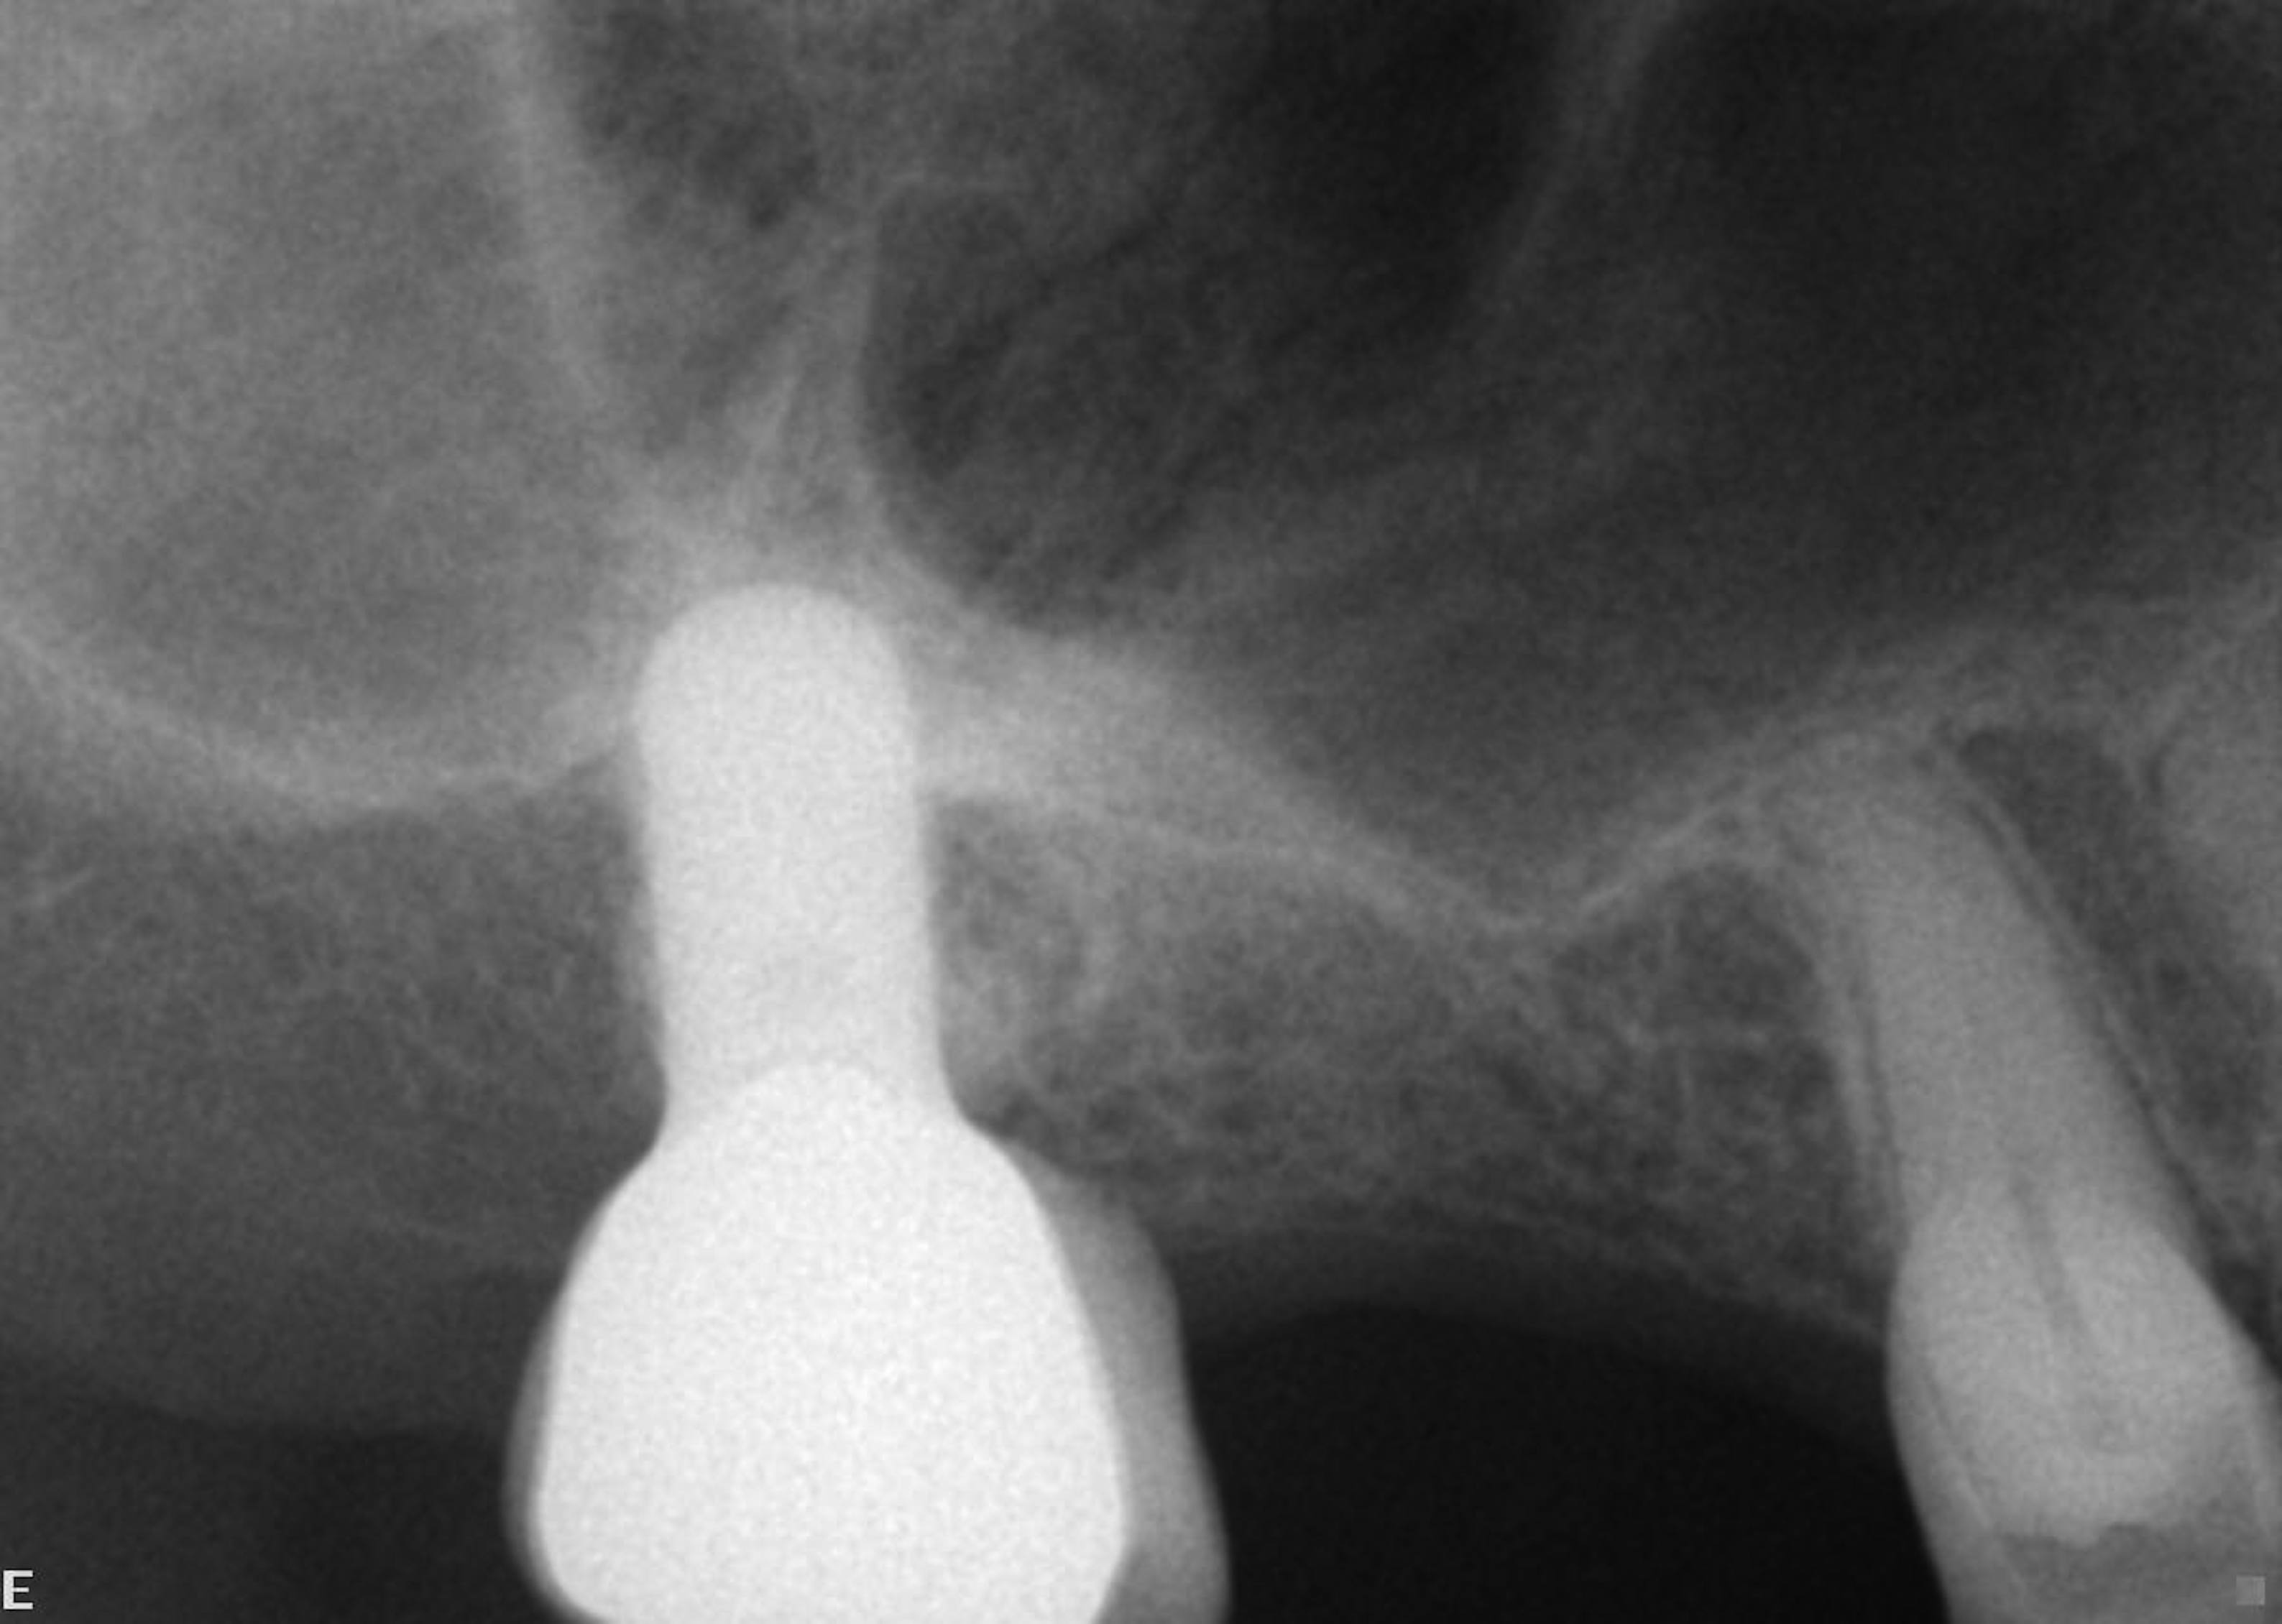

A patient who had received treatment 10 years ago for implants in the mandibular arch said her general dentist wanted to place an implant in site No. 3, using a hammer. Although that clinician believed the site had sufficient bone based on a periapical x-ray findings (Figure 21), the findings from a cross-sectional computed tomography scan helped determine that she had less than 3 mm of bone in the ridge (Figure 22). Froum et al14 and Tarnow et al15 both demonstrated the efficacy of combining rhBMP-2/ACS with mineralized bone allograft in sinus graft procedures. Marx et al16 demonstrated the combination of this growth factor with mineralized allograft and PRP to reconstruct severe maxillary defects. Given the 4 mm of minimal requirement for simultaneous implant placement, the author performed a lateral window sinus graft. An absorbable collagen sponge hydrated with rhBMP-2 was combined with mineralized bone allograft and used to obturate the site after reflection of the Schneiderian membrane along the medial sinus wall. A portion of the rhBMP-2/ACS was adapted over the grafted window osteotomy (Figure 23). After healing for approximately 5 months, the patient received a computer-guided implant surgery (Figure 24). The implant was restored with a screw-retained crown after a healing period of approximately 3 months.

The pretreatment radiograph suggesting more than 2 mm of subantral alveolar bone.

Figure 21

Cross-sectional view of the edentulous site demonstrating minimal bone height below the sinus floor.

Figure 22